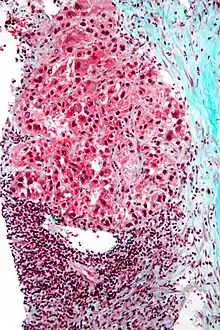

Liver micrograph showing abundant Mallory bodies, as seen in alcohol use disorder. Mallory bodies in hepatocellular carcinoma. Trichrome stain.

Mallory bodies in hepatocellular carcinoma. Trichrome stain.